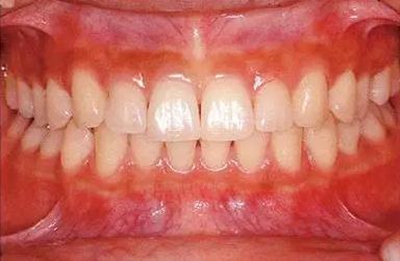

18歲男性的健康口腔內(nèi)部

圖為18歲男性,無(wú)特殊全身疾病,不抽煙。持續(xù)保養(yǎng)10年。牙菌斑控制比以前好,因刷牙稍稍過(guò)度臉頰側(cè)有牙齦萎縮傾向,但牙齒及牙周組織仍保健康

28歲女性的健康口腔內(nèi)部

圖為28歲女性,無(wú)特殊全身疾病,不抽煙。10年前來(lái)院就診保養(yǎng)3年,期間中斷過(guò),現(xiàn)又開始。齲壞風(fēng)險(xiǎn)高,當(dāng)初初診時(shí)已有好幾顆牙的鄰面有填充物,再填充了3牙的鄰面齲,現(xiàn)牙周組織健康。

65歲男性的健康口腔內(nèi)部

65歲男性。糖尿病與高血壓病史,目前治療中,40歲左右戒煙。有唾液減少傾向,但目前尚未見對(duì)牙齒及牙周組織的影響。初診時(shí)齲齒治療后,來(lái)院就診保養(yǎng)10年,雖因刷牙過(guò)度有牙齦萎縮,但牙齒及牙周組織仍保健康。如可妥善維持菌斑控制,則可維持牙周組織健康,不會(huì)減少牙周組織。